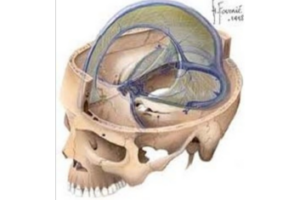

- Estudio de movimientos intrínsecos del cráneo: Diferenciar entre movimientos causados por estructuras inferiores y deformaciones propias del cráneo.

El curso se desviará de algunas ideas osteopáticas tradicionales, centrándose en los principios RPG y respetando los descubrimientos actuales en ciencias médicas. Además, se abordarán las estructuras intracraneales y su influencia en la postura, destacando la importancia de la duramadre y las membranas de tensión recíproca en el equilibrio de tensiones y la salud del sistema nervioso central.